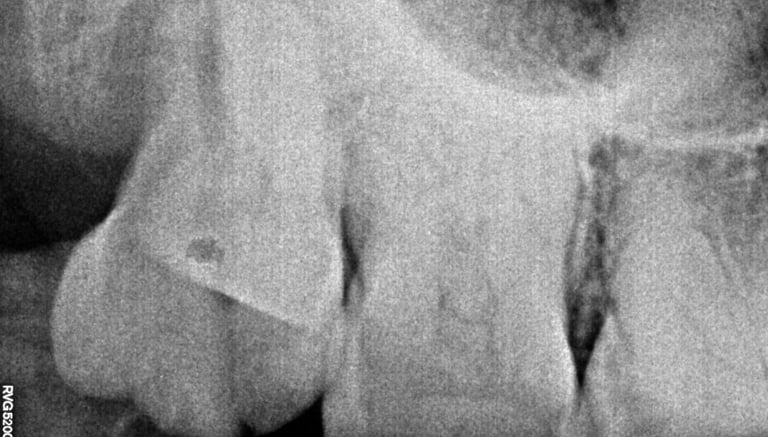

Root Canal Treatment near Shyamal, Ahmedabad

Before

After

All images shown here represent real clinical cases treated at our dental clinic with patient consent.

At Shree Dental Care, we focus on gentle, precise, and well-planned root canal treatment to remove infection, relieve pain, and preserve your natural tooth structure.

Patients from Shyamal and nearby areas of Ahmedabad visit our clinic for comfortable root canal procedures carried out using modern techniques and strict hygiene protocols. The treatment helps eliminate infection from inside the tooth, prevents further damage, and restores normal chewing function.